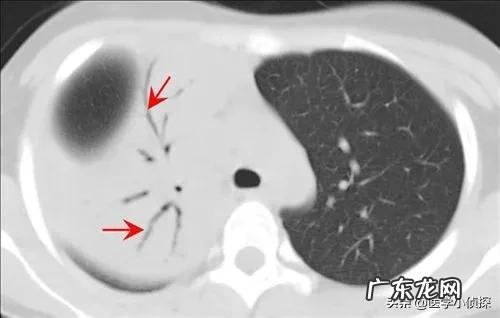

以及上面这种混杂密度的磨玻璃结节 , 就是其中含有部分实性成分 。

文章插图

只不过是不管是实性结节 , 还是像磨砂玻璃那样的 , 似透非透的那种结节 , 只是它的大小≤2cm , 甚至<1cm , 我们医生称之为肺结节 , 再大一点就不是了 , 那就叫做肺肿块了!